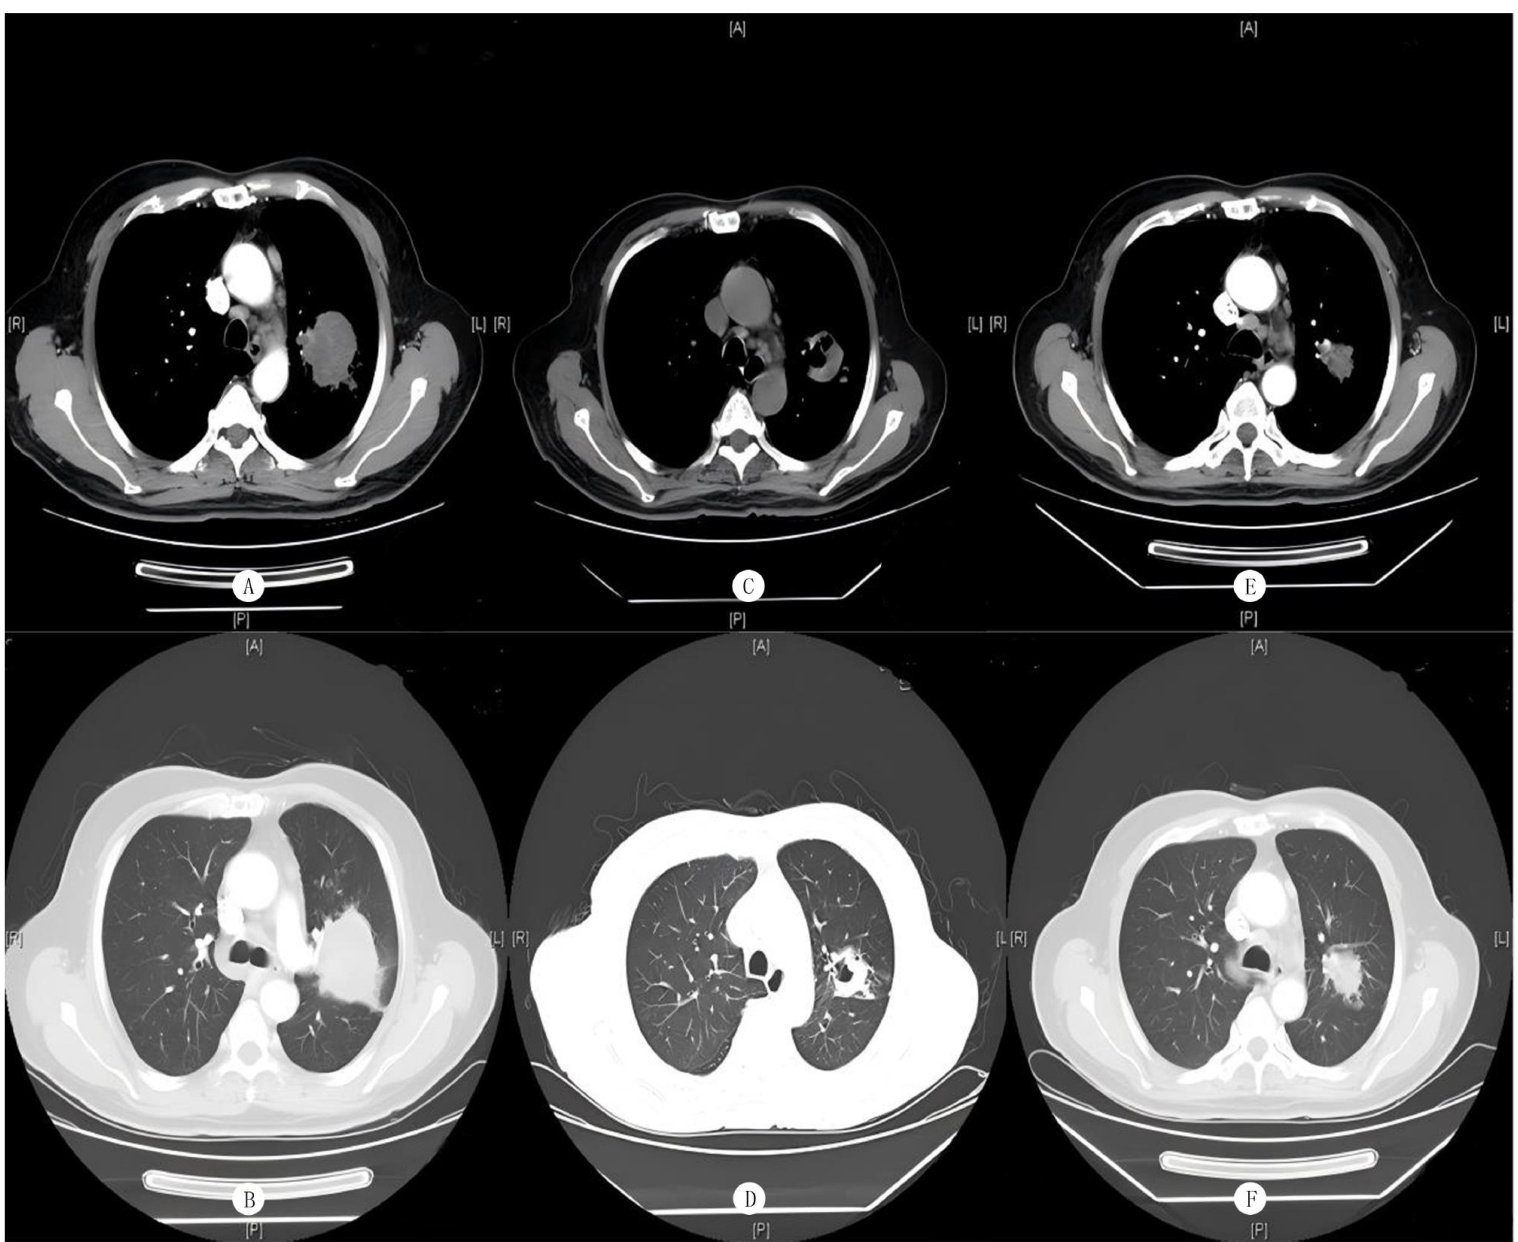

患者,男,69岁,因“刺激性干咳、咳血2月"于2021年2月25日初诊于我院。行胸部增强CT检查提示左肺上叶有一团块影,约为5.5cm×5.0cm×4.3cm 大小,不均匀强化,与左肺动脉干关系紧密,左肺上叶舌段堵塞性不张;同时多发纵隔淋巴结肿大(图1A、B)。PET-CT检查提示左肺上叶占位, SUVmax 约7.6;主动脉弓旁多个淋巴结肿大, SUVmax 约2.7。(剩余4395字)